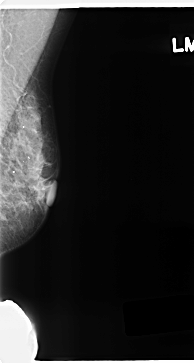

C_0221_1.LEFT_MLO

LEFT_MLO LINES 4712 PIXELS_PER_LINE 2512 BITS_PER_PIXEL 12 RESOLUTION 50 NON_OVERLAY